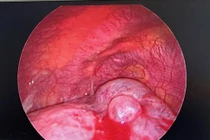

Hình ảnh tổn thương trong mổ - Ảnh BVCC

Sau hội chẩn liên chuyên khoa, các bác sĩ đã giải thích tình trạng bệnh, chỉ định phẫu thuật nội soi lồng ngực cắt kén khí phổi - giải pháp tối ưu nhằm loại bỏ tổn thương, bảo tồn phổi lành và ngăn ngừa các biến chứng nguy hiểm.

Ca phẫu thuật diễn ra trong một giờ, toàn bộ kén khí được cắt bỏ an toàn bằng phương pháp nội soi. Những giờ chờ đợi bên ngoài phòng mổ của người thân là khoảng thời gian đầy hồi hộp - cho đến khi nhận được tin ca phẫu thuật thành công.